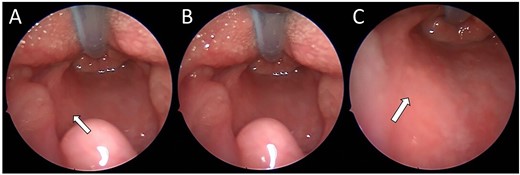

A 13-week-old child was acutely referred to the tertiary paediatric ENT team with stridor. The child had altered breathing for 2 weeks, initially treated as croup. On admission, the child had a tracheal tug, intercostal recessions and significant stridor. A 10 cm facial cutaneous plaque haemangioma was noted. Intravenous dexamethasone was commenced and micro-laryngoscopy showed a subglottic haemangioma occupying 40% of the airway, equivalent to Myer-Cotton classification Grade 1 (Fig. 1). Oral propranolol was commenced at 1 mg/kg/day in three divided doses as per local protocol increasing to 2 mg/kg/day once treatment was established. No neck lesion was apparent on clinical examination.

(A) Endoscopic (MLB) photographs of the supraglottic region. (B–C) Endoscopic (MLB) photographs of glottic and subglottic regions highlighting the presence of a subglottic haemangioma.